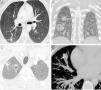

We report the case of a 30-year-old patient, diagnosed in 2011 with vascular Ehlers-Danlos syndrome (also called Ehlers-Danlos syndrome type IV), who had presented several episodes of bilateral pneumothorax in the previous 2 years. Although the most significant complications presented by this patient were associated with the formation and spontaneous rupture of aneurysms in multiple arteries (carotid, renal, splenic, vertebral, etc.), since 2013 a wide variety of pulmonary nodules had also appeared on incidental radiological images, including solid nodules (Fig. 1A), subsolid nodules (Fig. 1B), cavitary nodules (Fig. 1C), and nodules containing calcifications (Fig. 1D).

(A) Chest CT axial image (pulmonary parenchymal window) from 2013, showing a solid nodule in the right lower lobe (arrow). (B) Chest CT coronal image of the scan of the (pulmonary parenchymal window) from 2014, showing the appearance of 2 nodules in the right lung: one solid (arrow) and other subsolid with mainly ground glass attenuation and a small, solid core (asterisk). (C) Chest CT axial image (pulmonary parenchymal window) from 2016 showing the appearance of 2 cavitary lung nodules in the right pulmonary apex (arrows). Note that the most lateral nodule has non-centered cavitation with half-moon morphology. (D) Chest CT axial image (mediastinal window) from 2017 in which linear calcification (arrow) has appeared within a solid nodule in the middle lobe.